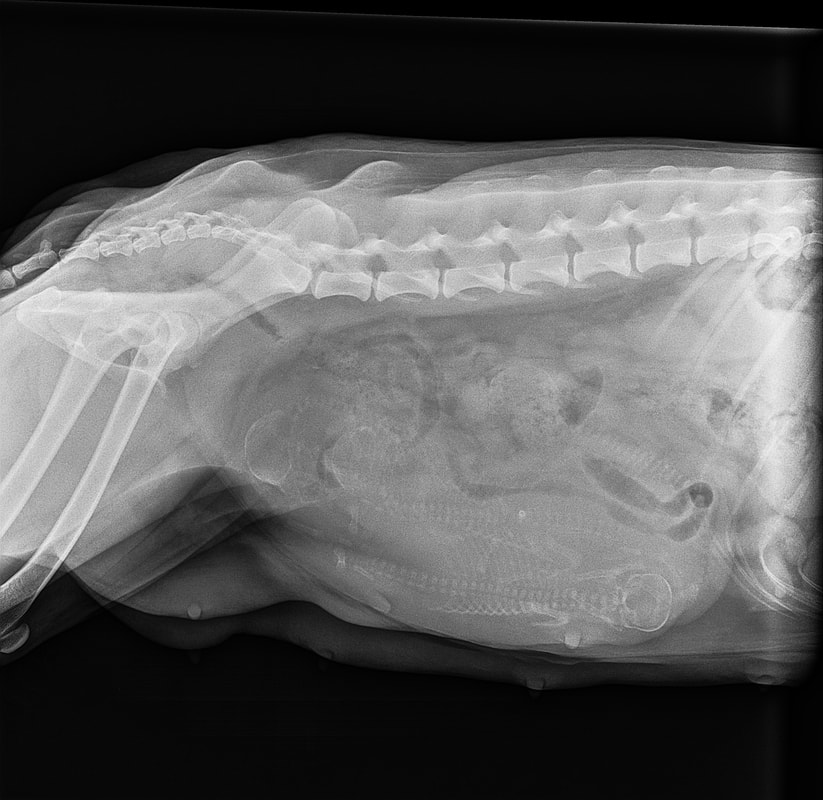

This is day 55! The x-ray showed four! We were so excited!